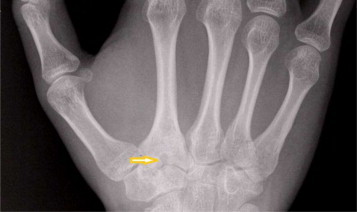

The radiograph of the right hand revealed a slightly expanded base of the second metacarpal with a cyst formation (Fig. 1). An MRI scan was arranged to rule out the possibility of any occult ganglions or an injury to the scapholunate ligament (due to previous surgery). The scan reported an abnormal second metacarpal base with profound oedema and focal area of bone irregularity and a sclerotic margin. A provisional diagnosis of a Brodie's abscess was suggested by the radiologist (Fig. 2). The inflammatory markers showed normal white cell count and CRP of 13.

Fig. 1.

The radiograph of the hand showing a well circumscribed cystic lesion in the base of second metacarpal.